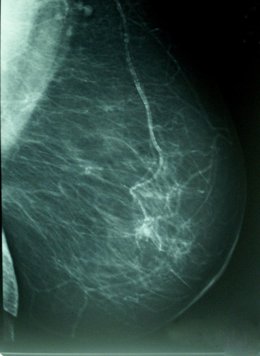

El estudio, publicado en la revista 'Breast Cancer Research and Treatment', explora la influencia de determinadas características con dicha densidad - la proporción de tejido radiológicamente blanco en la mamografía-, que es reconocido como un marcador de riesgo de cáncer de mama.

La investigación, realizada sobre una muestra 3.574 mujeres con edades comprendidas entre los 45 y los 68 años, analiza la influencia de ciertas características del nacimiento y la infancia de las mujeres con su densidad mamógrafica, un importante marcador de riesgo para cáncer de mama.

Aunque la densidad mamográfica tiene un claro componente hereditario, varía también en función de los factores de riesgo conocidos del cáncer de mama, como la edad al primer parto y el número de hijos.